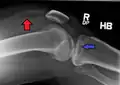

A severe tibial plateau fracture with an associated fibular head fracture